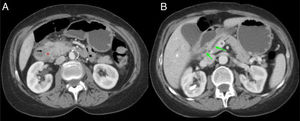

En los casos de PS en su forma segmentaria (no exclusiva del surco, sino que se extiende a la cabeza pancreática), la afectación se evidencia como una masa hipodensa en la cabeza pancreática que puede asociar en algunos casos dilatación del CPP y cierto grado de estenosis del colédoco con dilatación retrógrada de la vía biliar intra- y extrahepática1,2,7. En casos en los que se produzca estenosis del CPP, esta suele ser progresiva y regular, a diferencia de lo que ocurre en los casos de ACP donde la estenosis suele ser irregular y abrupta7. Esta masa inflamatoria en el surco PD presenta un realce tardío y progresivo tras la administración de contraste, debido a la inflamación crónica y el componente fibrótico7,10,11. Además, es frecuente que el duodeno presente cierto engrosamiento mural en su aspecto medial y formaciones quísticas en la pared del duodeno o incluso en el propio surco PD (fig. 4)3,7,10.

Varón de 60 años con síndrome constitucional. Corte axial (A) y coronal (B) del abdomen con contraste intravenoso en fase portal. Dilatación del conducto pancreático principal (flecha roja, A y B) y presencia de calcificaciones en la cabeza-cuerpo del páncreas (asterisco rojo, A y B), en relación con pancreatitis crónica. Ocupación del surco pancreaticoduodenal (asterisco verde, B) y engrosamiento mural duodenal con lesiones quísticas en su interior (flecha verde, A y B). Hallazgos compatibles con pancreatitis del surco.

Al ser la PS un tipo de pancreatitis crónica, el páncreas suele presentar los cambios crónicos típicos: atrofia con sustitución grasa, calcificaciones o cálculos en el interior del CPP (fig. 4)4,7,10.